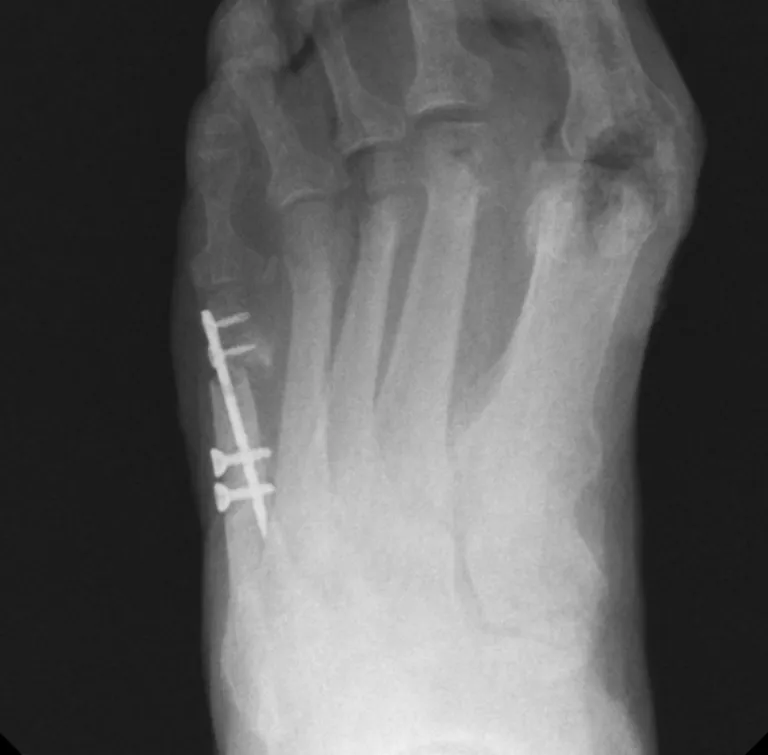

The Javelin System provides a streamlined, comprehensive solution for Tailor’s Bunion corrections.

A targeting jig is provided in the system to allow for easy insertion of bi-cortical screws targeting the plate holes in the intramedullary canal.

The system consists of an intramedullary titanium alloy plate and screws that provide stable fixation for 5th metatarsal bone fragments following a transverse osteotomy.

The plate’s low-profile design enables the user to achieve maximum medial correction of the capital fragment.